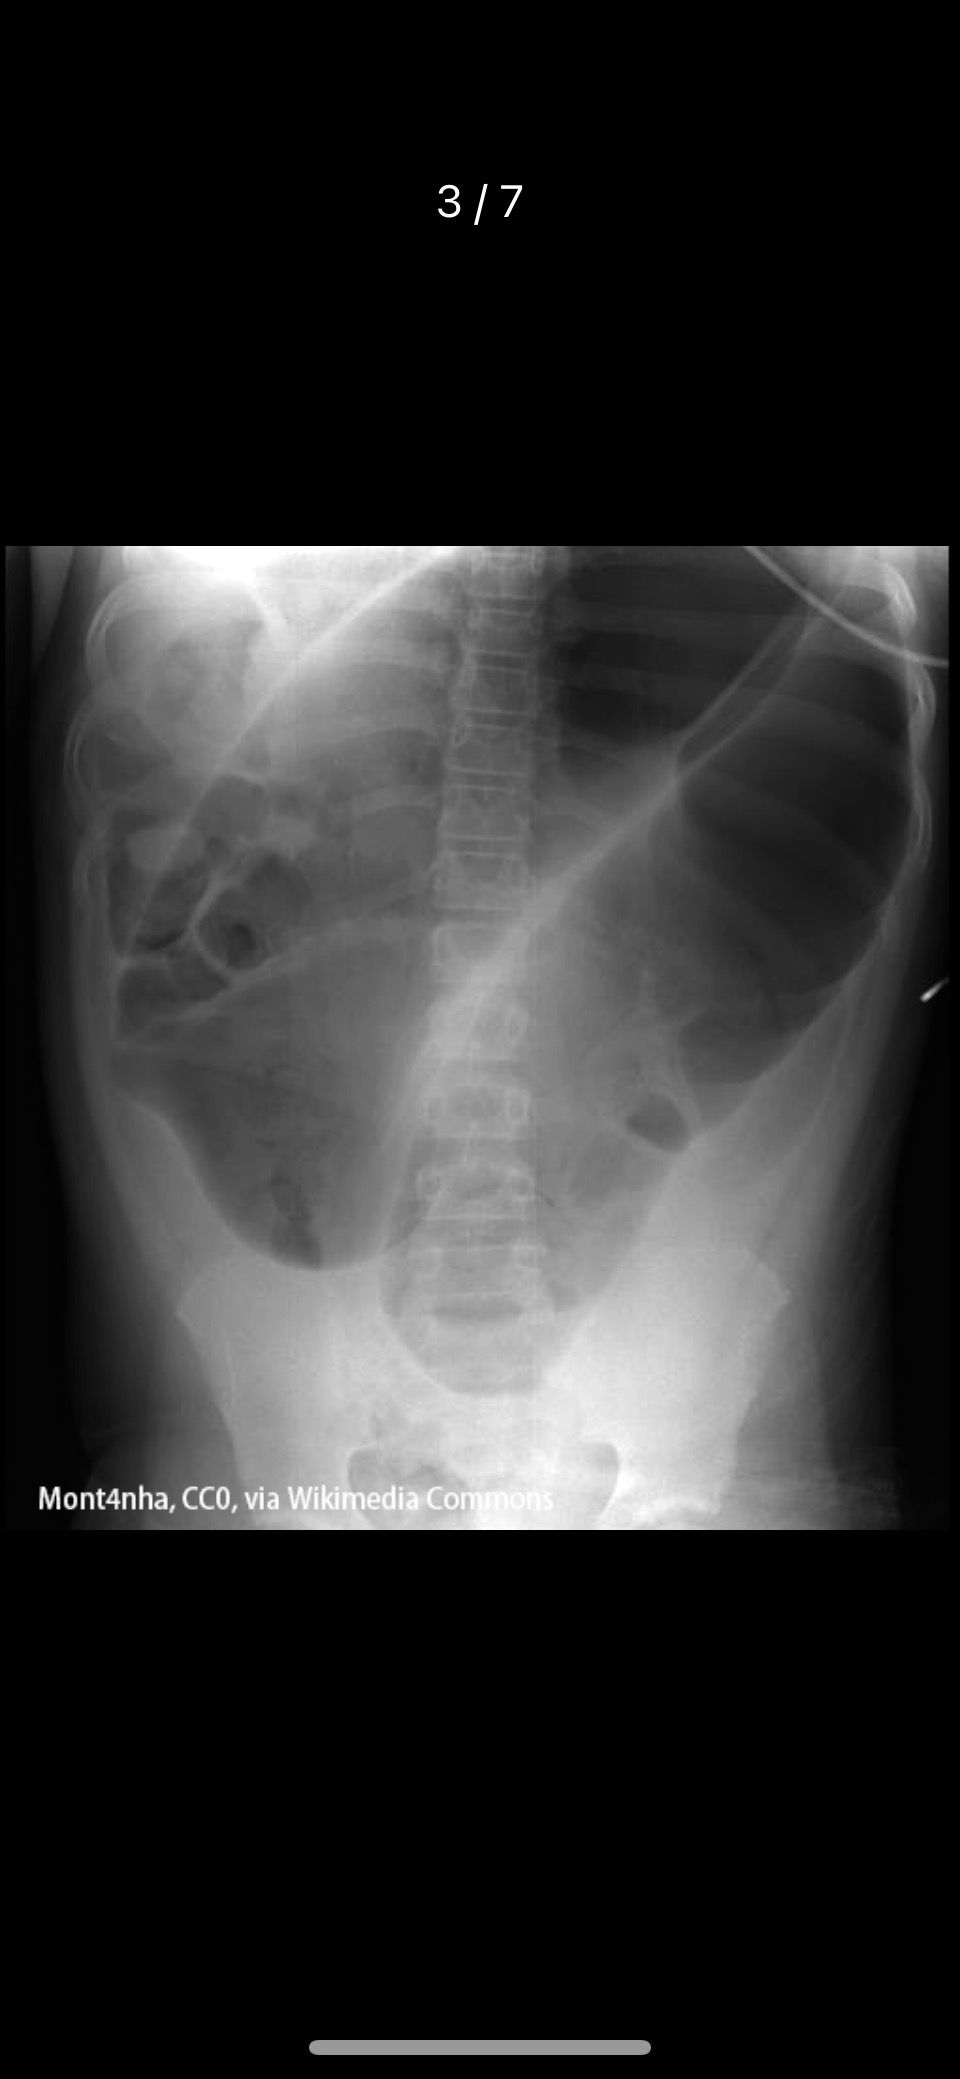

青年女性患者,腹痛、腹胀伴低热3个月,突发脐周绞痛、呕吐,无排便、排气(提示急性肠梗阻),最可能的诊断为结核性腹膜炎并肠梗阻。腹部X线平片可显示肠系膜淋巴结钙化影,有助于结核性腹膜炎的诊断;肠梗阻在腹部平片上可见阶梯状的液气平面,因此,该患者的首选检查是立位腹部X线平片(B对)。结肠镜检查(A错)主要用于肠道内病变的诊断,肠梗阻时一般不用。腹部B超(C错)多用于肝、脾等实质性脏器的检查,对胃肠道等空腔器官的显示效果不佳。腹部CT(D错)与MRI(E错)可详尽显示腹腔内病变情况,但其耗时长,价格较贵,不做为首选检查。

肠梗阻首选检查就是立位X线

低位梗阻:回肠梗阻。呕吐晚次数少、初期为胃内容物,后期为粪样物,腹胀明显、阶梯状液气平面。结肠内少量积气提示小肠低位梗阻,说明小肠气体很多 - 高位

高位梗阻:空肠梗阻,鱼肋征(鲤鱼旗在高空中)。呕吐早次数多、为胃内容物,腹胀腹痛不明显、粘膜环形皱襞(鱼刺骨状)。空场粘膜皱壁更丰富,肠管扩张的时候,两空肠肠壁叠加,形成高密度影的“鱼骨”,两边的粘膜皱壁是高密度影,构成了“鱼刺”